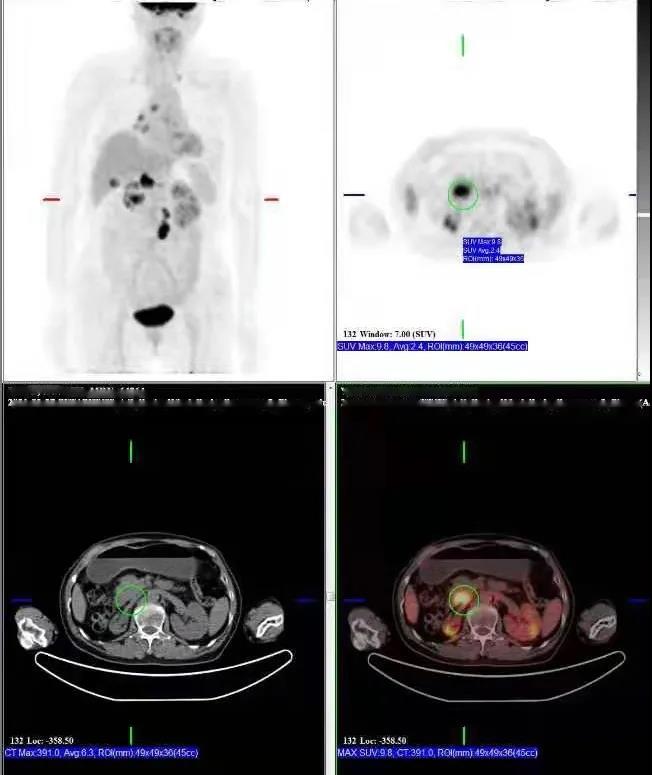

PET/CT檢查所見:胰腺鉤突見一低密度灶,動脈期及靜脈期強(qiáng)化稍低于周圍正常胰腺組織,延遲期掃描病灶與正常胰腺呈等密度,病灶邊界欠清晰,大小約2.6×3.7cm,F(xiàn)DG攝取增高,SUVmax:9.8。胰周脂肪間隙清晰,胰管未見擴(kuò)張。肝門區(qū)及腹膜后見多發(fā)腫大淋巴結(jié)影,增強(qiáng)掃描呈環(huán)形強(qiáng)化,最大者大小約2.2×3.5cm,F(xiàn)DG攝取增高,SUVmax:17.0。膽總管明顯擴(kuò)張,呈囊狀改變,最寬處約直徑4.5cm。

提示: 胰腺鉤突病變,糖代謝增高,考慮胰腺癌可能性大

肝門區(qū)及腹膜后淋巴結(jié),糖代謝增高,考慮轉(zhuǎn)移性淋巴結(jié)

先天性膽管擴(kuò)張